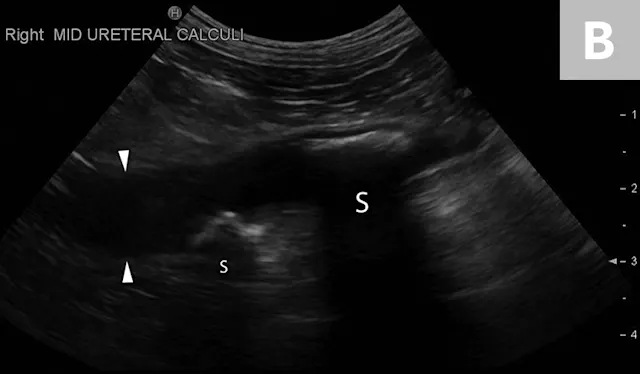

Ureteral calculi are a common cause of ureteral obstruction; localization of ureteral calculi is imperative prior to choosing appropriate management. While ureteral calculi have been reported as the most common cause of ureteral obstructions, other causes such as iatrogenic ligation, blood clots, tumor, strictures (congenital and acquired), solidified blood stones, and a circumcaval ureter have been reported.4-7

The obstruction can be located at any point of the ureter and can vary in severity. Normal ureters are typically not seen on ultrasonography due to their small size. The easiest way to locate a dilated ureter is to trace the ureter from the renal pelvis. In most cases, the ureter is dilated proximal to the site of an obstruction and tapers to a more normal appearance distal to the site of obstruction. Imaging can also reveal retroperitoneal effusion which can result from ureteritis and possible urine leakage.

Clinical signs associated with ureteral calculi may range from chronic non-specific signs to acute or chronic renal failure. The presence of hydronephrosis can be highly suggestive of a ureteral obstruction (Figure 6).